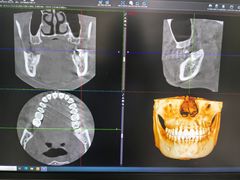

• 医疗健康 齿科 体检中心

口腔齿科 体检中心 医院 药店 中医 宠物医院 整形 妇幼医院 其他医疗

• 北京大学口腔医院(第三门诊部)

• -北京大学口腔医院(第三门诊部)